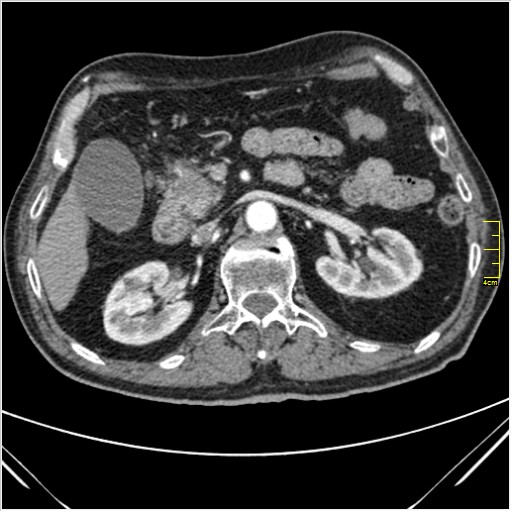

Мужчина 62 года с желтухой

Опухоль головки поджелудочной железы, расширение холедоха и панкреат. протока (Double Channel sign)

Карциномы панкреас гиподенсны на КТ с болюсом, т.к. содержать много соединительной и фиброзной ткани, в отличие от нормальной ткани железы, которая (как любая железа) хорошо васкуляризирована. Поэтому если видим в панкреас солидное гиподенсное образование - всегда настораживает на предмет рака. Второй момент: обязательная оценка взаимоотношения опухоли к ВБА и ВБВ, на предмет оценки операбельности.